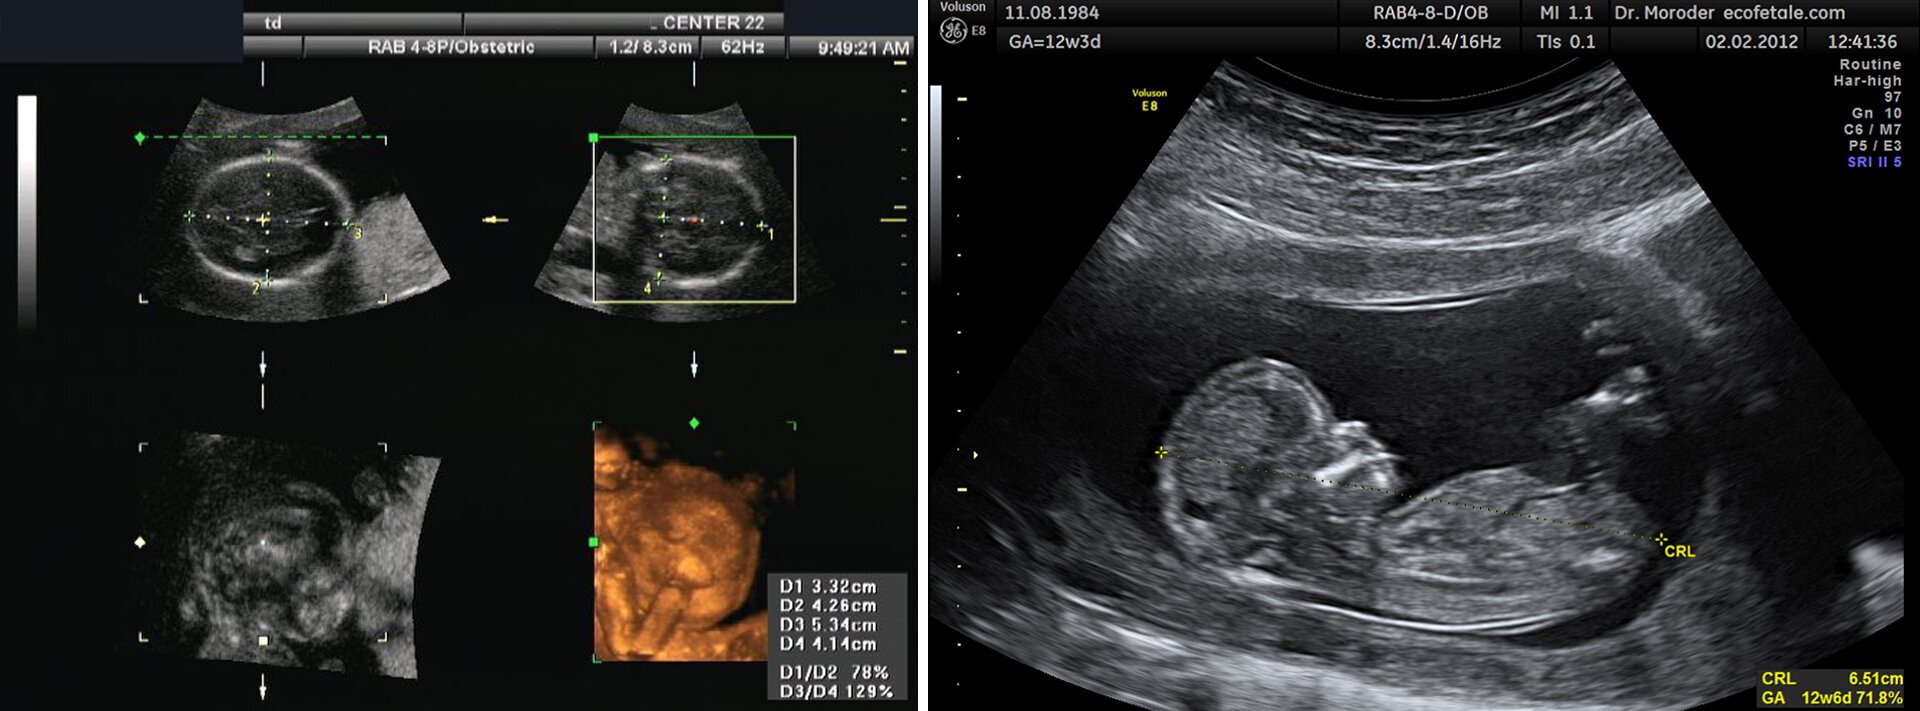

Obrazy USGŹródło: DuBose, Moroder, Krzysztof Jaworski, dostępny w internecie: https://commons.wikimedia.org, licencja: CC BY-SA 3.0.w rehabilitacji medycznej (fizykoterapia);

Najbardziej znanym przykładem zastosowania ultradźwięków w medycynie jest ultrasonografia (USG). Jak wspomnieliśmy, fala ulega odbiciu na granicy dwóch ośrodków. Ośrodki te różnią się gęstością i prędkością rozchodzenia się dźwięków. Ponieważ różne organy w ciele człowieka mają różne wartości prędkości i gęstości, to fala ultradźwiękowa odbija się częściowo od granicy ośrodków i jest rejestrowana przez sondę. Fala przenika dalej w głąb danego organu i ulega znowu częściowemu odbiciu od następnej granicy. Kolejne odbite impulsy są rejestrowane i dają obraz wewnętrznej budowy ciała człowieka. Wiele osób zastanawia się, czemu służy żel, którym smaruje się powierzchnię skóry przed badaniem USG. Powodem tego jest to, że w powietrzu fala rozchodzi się z zupełnie inną prędkością niż w skórze i ulegałaby bardzo silnemu odbiciu od powierzchni skóry. Żel ma prędkość rozchodzenia się dźwięków zbliżoną do prędkości w skórze, odbicie jest znikome i fala może wejść w głąb organizmu. Warto podkreślić, że częstotliwość drgań podczas przechodzenia przez różne ośrodki nie zmienia się. Zmienia się natomiast długość fali związana z wartością prędkości, z jaką fala się rozchodzi w danym środowisku.